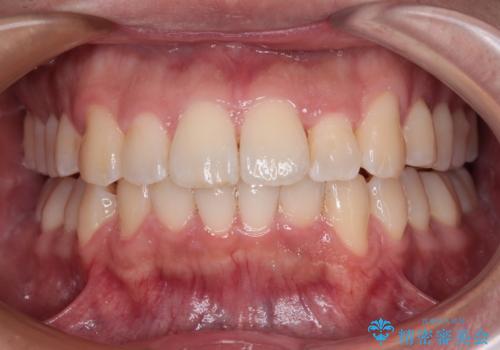

前方に捻れた前歯を治したい インビザライン矯正治療

- 前歯のデコボコを治したいとのことで来院された患者様です。

上下顎ともに歯列全体の後方移動とIPR(歯と歯の間を削る)によってデコボコが解消するように設計し、インビザラインにより治療を行うこととしました。